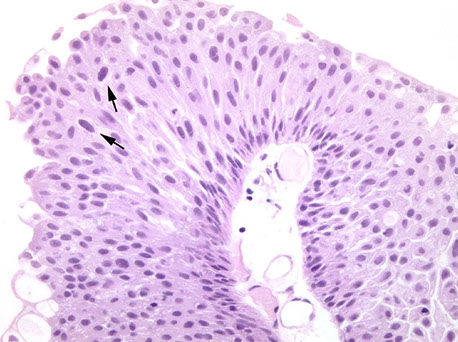

Reactive urothelium (Dr. Epstein)

Reactive urothelium

More reactive urothelium

Reactive Urothelial Atypia

• Acute or chronically inflamed urothelium

• Vesicular uniformly enlarged nuclei with central

prominent nucleoli.

• Mitotic figures may be common.

• History of instrumentation, infection, stones, therapy